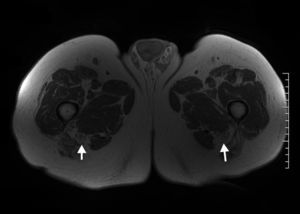

La lipomatosis del nervio ciático, también conocida como hamartoma fibromatoso, es una condición seudotumoral rara caracterizada por el engrosamiento fusiforme de un nervio por hipertrofia anómala del tejido fibroadiposo. La apariencia de esta entidad en la RM es patognomónica. En las secuencias ponderadas en T1 muestra el patrón fascicular del nervio, hipointenso, surcado por tejido hiperintenso similar a la señal de la grasa que se distribuye uniformemente entre las fibras del nervio. En las secuencias ponderadas en T2, y en particular en aquellas con saturación grasa o STIR (short tau inversión recovery), el nervio aparece homogéneamente hipointenso debido a la supresión del componente graso y a la baja señal del patrón fascicular normal. La cantidad de componente graso es variable43,44 (fig. 7).

Paciente de 73 años que presentaba parestesias leves en el territorio peroneo de ambos lados. En las imágenes ponderadas T1 se observa aumento de grosor del nervio ciático de ambos lados a expensas de una hipertrofia del componente graso intraneural, hallazgo compatible con lipomatosis bilateral del nervio ciático (flecha).